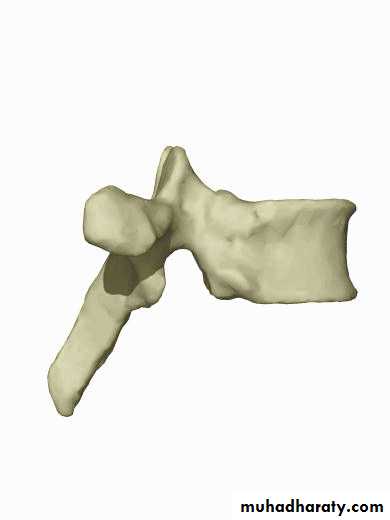

Cervical Vertebrae

Atlas (C1)

Axis (C2)C3-C7

Has two transverse foramen